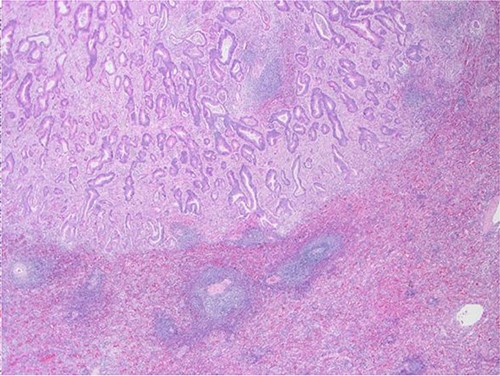

Surgical specimen: hysterectomy; microscopy, HE; endometrium and myometrium infiltrated by well-formed neoplastic glandular structures composed of cells with ‘pencillated’ and atypical nuclei, with nucleoli, apoptosis and mitotic figures, consistent with an intestinal origin (metastatic colorectal adenocarcinoma).

Surgical specimen: hysterectomy; microscopy, HE; endometrium and myometrium infiltrated by metastatic colorectal adenocarcinoma.